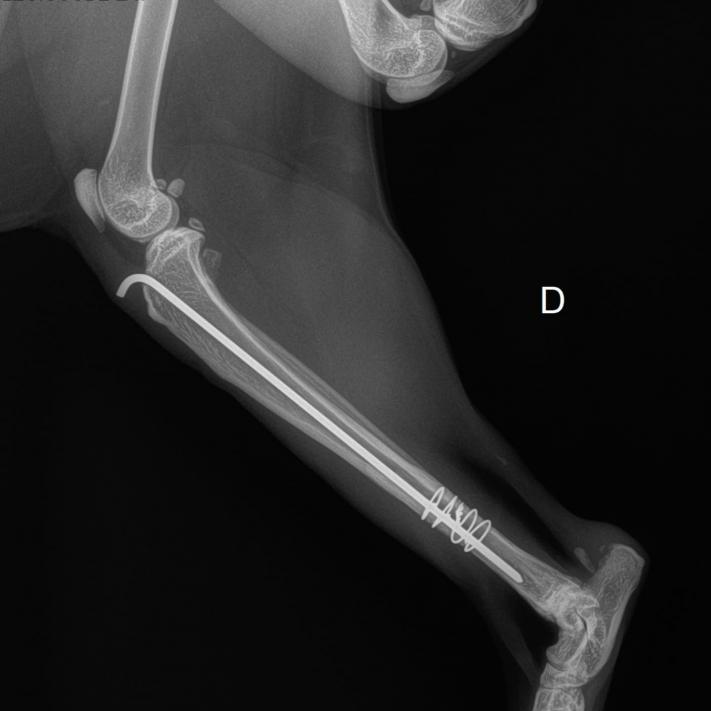

Exclusivement réalisées par le Dr. ROMAGNY, ce dernier proposera ses services afin de corriger chirurgicalement fractures, ruptures de ligaments croisés, luxations,...

- Des radiographies du squelette pour explorer différentes pathologies (fracture, fêlure, arthrose, tumeurs…)